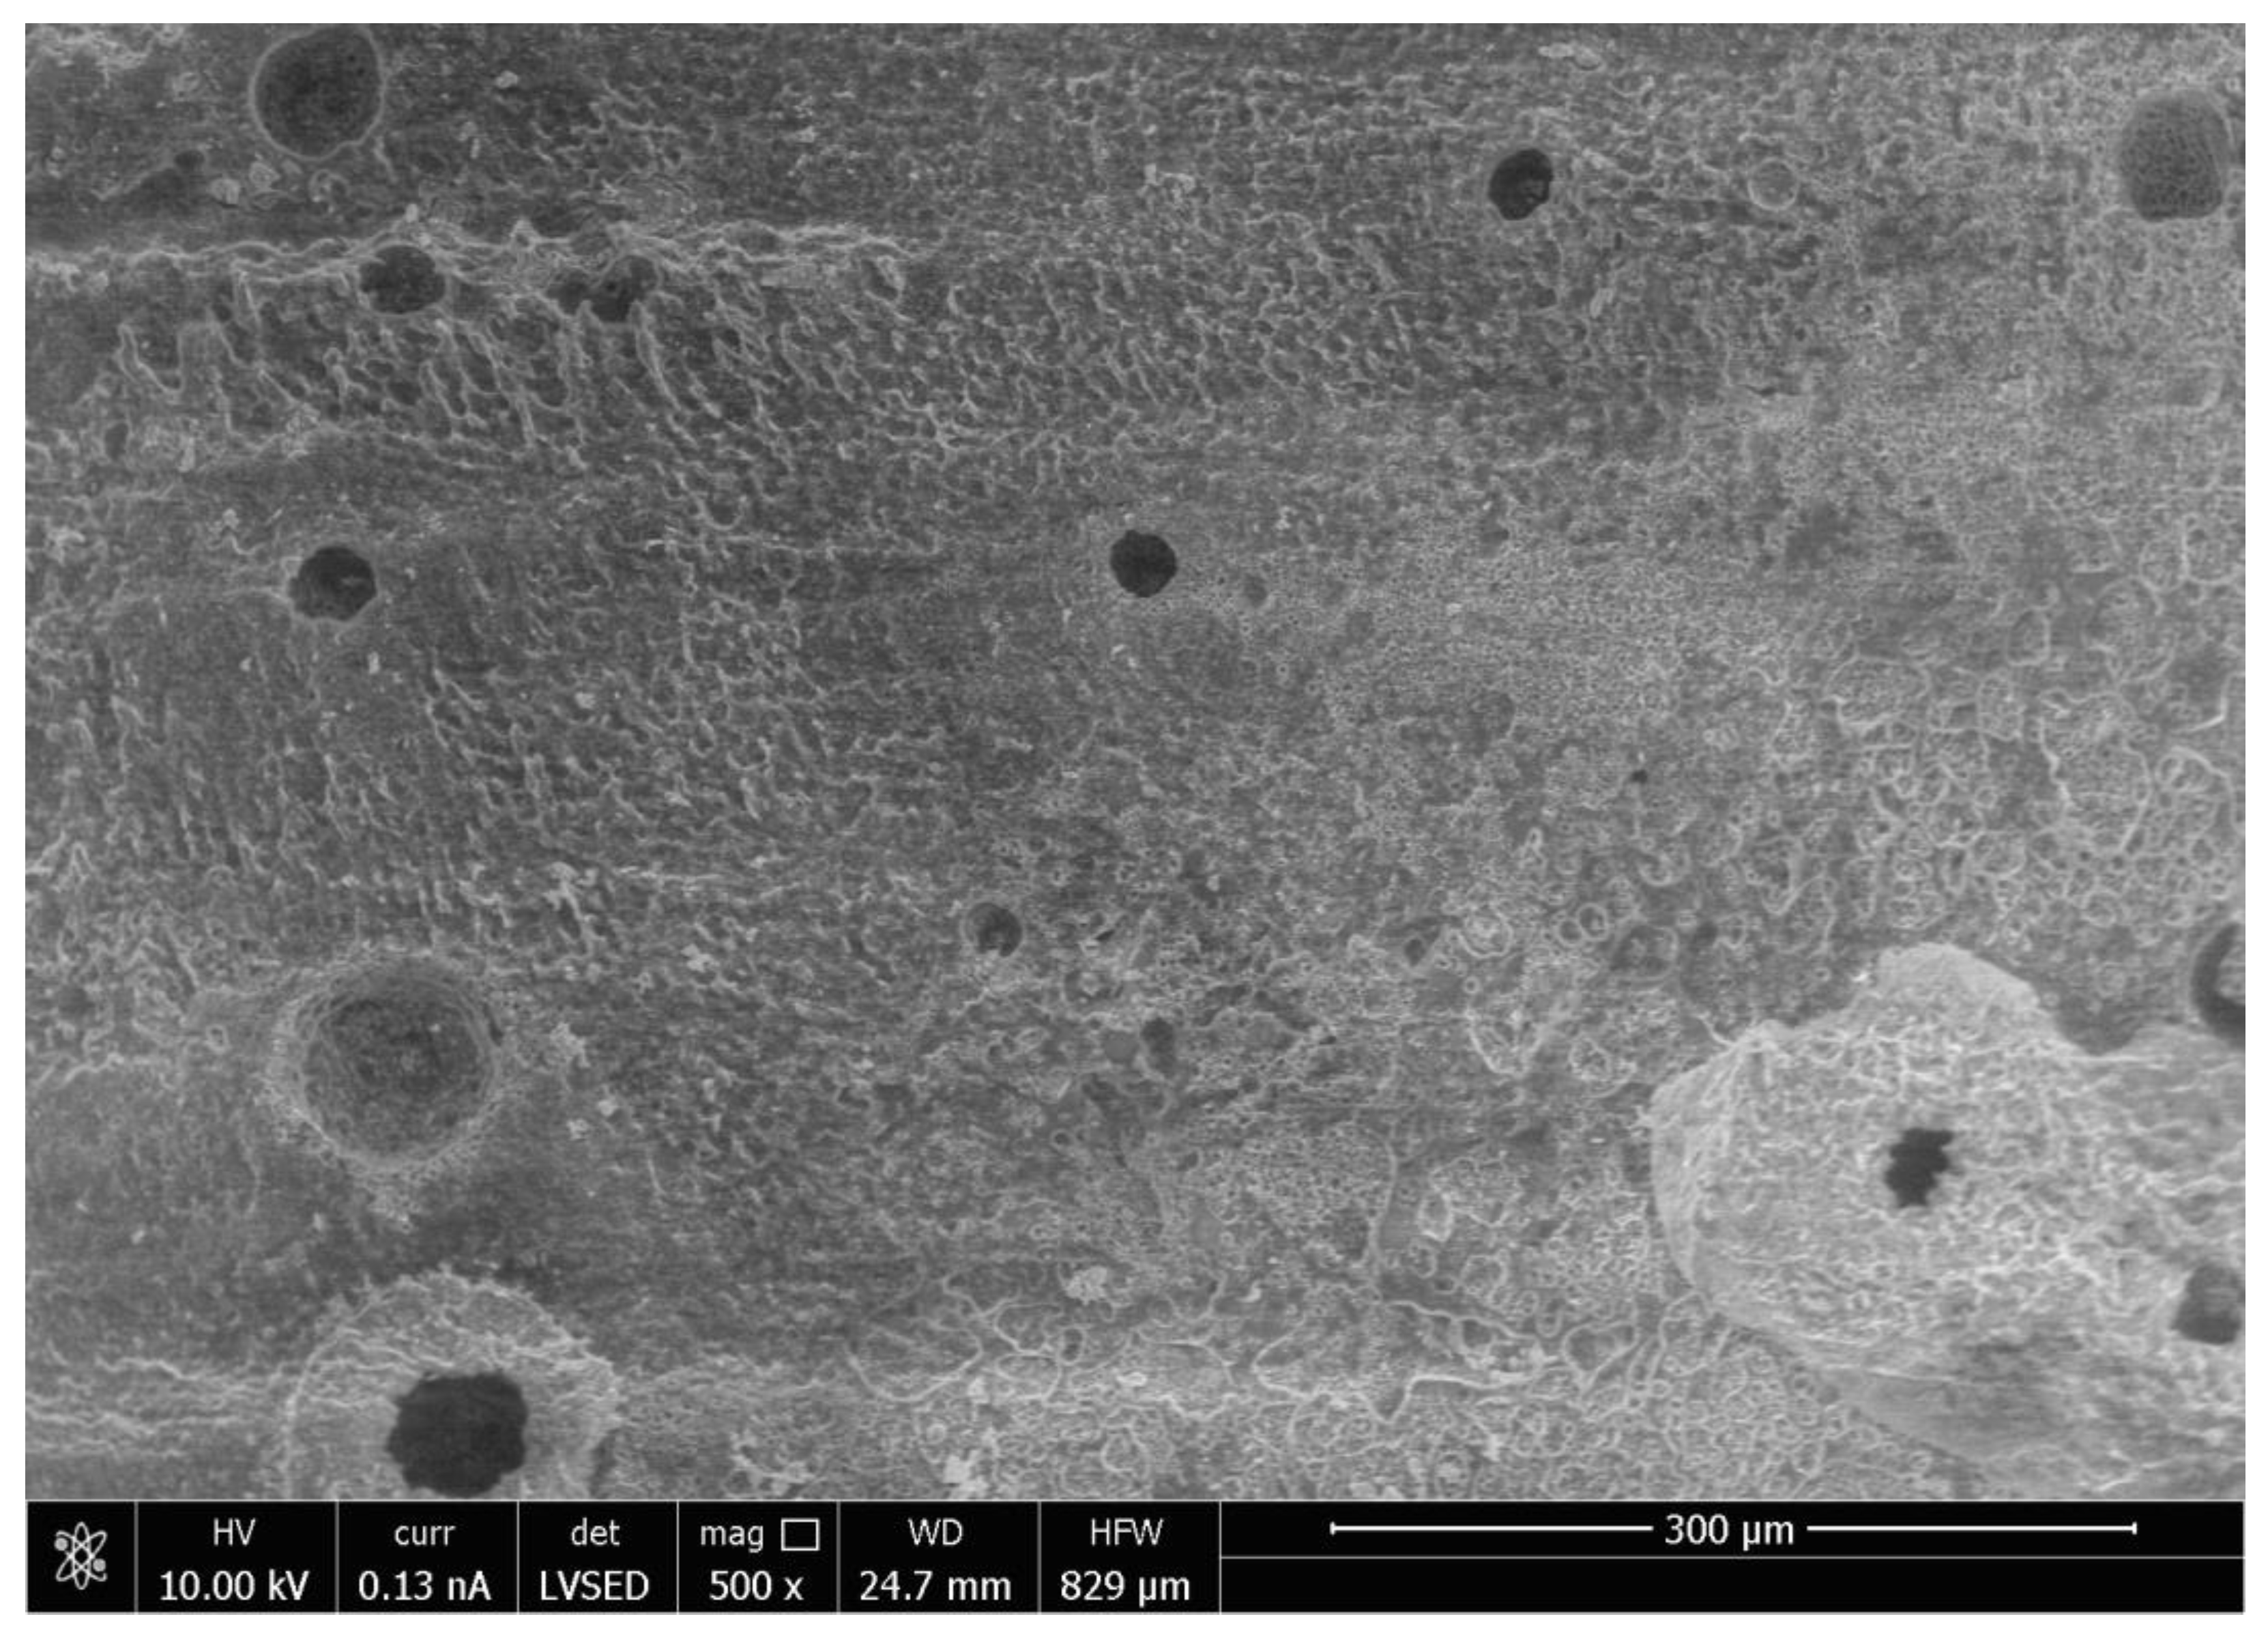

SEM analysis of the abutment teeth demonstrated rotary cutting streaks on the tooth surface at a low magnification of 500× (Figure 5). At higher magnifications (≥5000×), there were more openings of the dentinal tubules observed in the rotary handpiece removal group compared to the laser group. The dentin surface of the specimen from laser crown removal appeared to have a more intact smear layer and residual cement (Figure 6A,B). Crown specimens from the rotary group presented with more crack and crest lines at higher magnification levels (10,000×), indicating possibly more surface damage of the ceramic material compared to the laser group (Figure 7A,B).

Crown removal is a routine dental procedure. It should be noted that removal times for zirconia crowns with an air rotary handpiece can vary greatly depending on the provider’s experience, whereas removal time with the laser is likely dictated by laser settings, cement type and thickness, crown materials, and tooth anatomy/crown retention form [17]. Longer laser removal times may have been related to cement thickness associated with a prefabricated crown that requires a passive fitting concept, where more energy is required to ablate the thicker volumes of cement. Previous studies have shown that greater cement thickness is related to longer debonding time [17]. There are no visible external physical changes in the crown after being subjected to the laser crown removal procedure, thus allowing the reuse of the crown. The crown is destroyed following rotary handpiece removal. The SEM analysis of the ceramic material subjected to laser crown removal appeared intact, with no structural damage similar to previous reports [4,6,17,18]. A downside of the inability to observe changes in crown structure during laser removal is that it is difficult to determine when the crown is ready to be retrieved from the tooth and thus this may reflect in a longer time for crown retrieval.

Similar to previous studies, crown removal by laser does not appear to damage the retrieved crowns or the underlying tooth structure [3,6,18,30]. In our study, SEM analysis demonstrated that laser irradiation of zirconia crowns showed no underlying tooth damage and fewer surface irregularities of the crown surface compared to air rotary removal. Evidence of changes in tooth structure at low magnification following removal with a rotary handpiece proves there is a risk of damaging the tooth during crown removal. However, if a crown was to be retrieved due to recurrent caries, then the extent of the caries will impact the dentin surface and smear layer, irrespective of what crown removal technique is employed.

Figure 7. Scanning Electron Microscope Image of the Surface of the Zirconia crown at Magnification 10,000× Following Crown Removal with Rotary Handpiece (A) and Er,Cr:YSGG Laser (B).